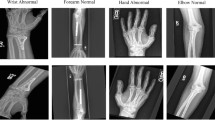

a The deep-learning system used an ensemble of 10 convolutional neural networks. To produce a prediction, radiographs are processed by each network in the ensemble, averaged, and then post-processed to generate an overall fracture determination and bounding boxes. b Example outputs for each of the 16 anatomical regions supported by the deep-learning system.